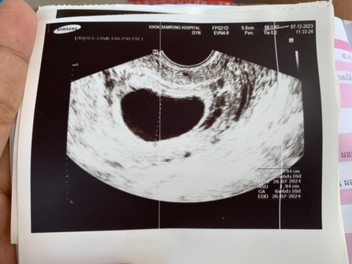

อัลตร้าซาวด์หน้าท้อง หมอเจอแต่ถุงตั้งครรภ์ 6w3d กังวลมากเลยค่ะกลัวท้องลม

ของเราซาวหน้าท้องไม่เจอคะ แต่ซาวทางช่องคลอดเจอตัวน้อง ซาวตอนได้6วีค6วัน ฝากรพ.รัฐ วันนี้ครบ8วีคแล้วคะ

ครั้งแรก 7-8 w ของเราไม่เจอ เจอ 12 w นับประจำเดือน แต่ในใบ 10w ไข่อาจจะตกช้าค่ะ รอก่อน

7 Week ยังไม่เจอตัวน้องเลยค่ะ เจอแต่ถูกตั้งครรภ์เหมือนกัน

6วีคถ้ายังไม่เจอตัวอ่อน ถือว่าผิดปกติมั้ยค่ะ กังวลมากค่ะ